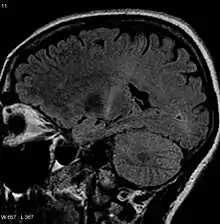

Because symptoms of ALS can be similar to those of a wide variety of other, more treatable diseases or disorders, appropriate tests must be conducted to exclude the possibility of other conditions. One of these tests is electromyography (EMG), a special recording technique that detects electrical activity in muscles. Certain EMG findings can support the diagnosis of ALS. Another common test measures nerve conduction velocity (NCV).[88] Specific abnormalities in the NCV results may suggest, for example, that the person has a form of peripheral neuropathy (damage to peripheral nerves) or myopathy (muscle disease) rather than ALS. While a magnetic resonance imaging (MRI) is often normal in people with early-stage ALS, it can reveal evidence of other problems that may be causing the symptoms, such as a spinal cord tumor, multiple sclerosis, a herniated disc in the neck, syringomyelia, or cervical spondylosis.[3][89]